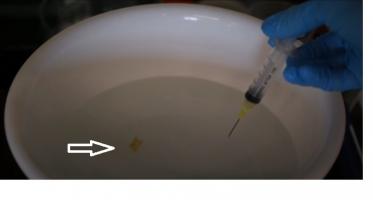

MÉDICAMENTS : L’administration par nanoparticules et par ultrasons